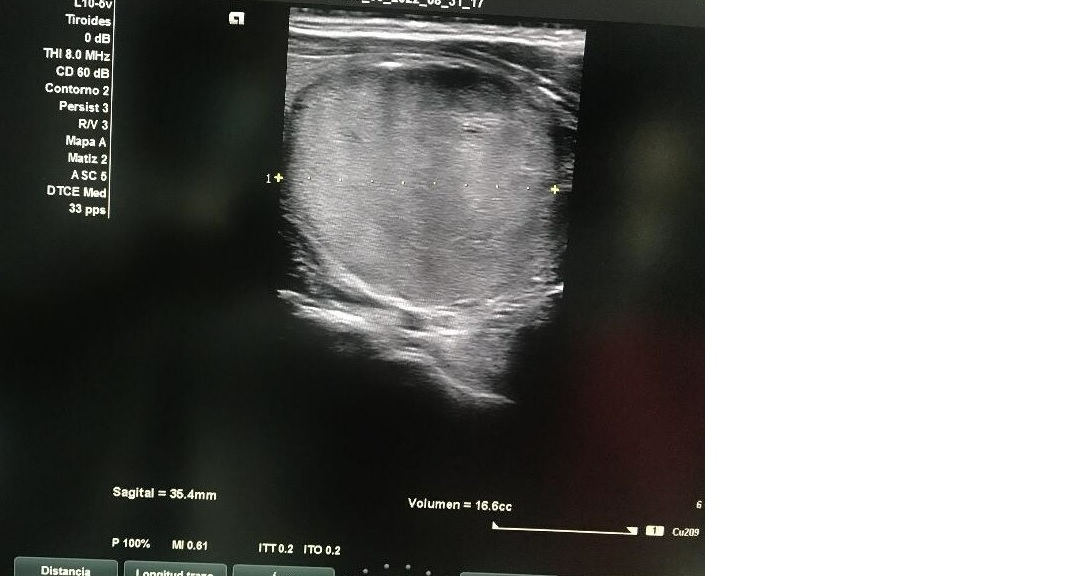

Ecografía tiroidea: Glándula tiroidea con ecoestructura homogénea en LTD con nódulo sólido en LTI con ocupación completa, hiperecogénico, bien delimitado con unas dimensiones de 3,5 x 3,5 x 4 con macrocalcificación en tercio superior con sombra acústica con vascularización de predominio periférico sin adenopatías cervicales.